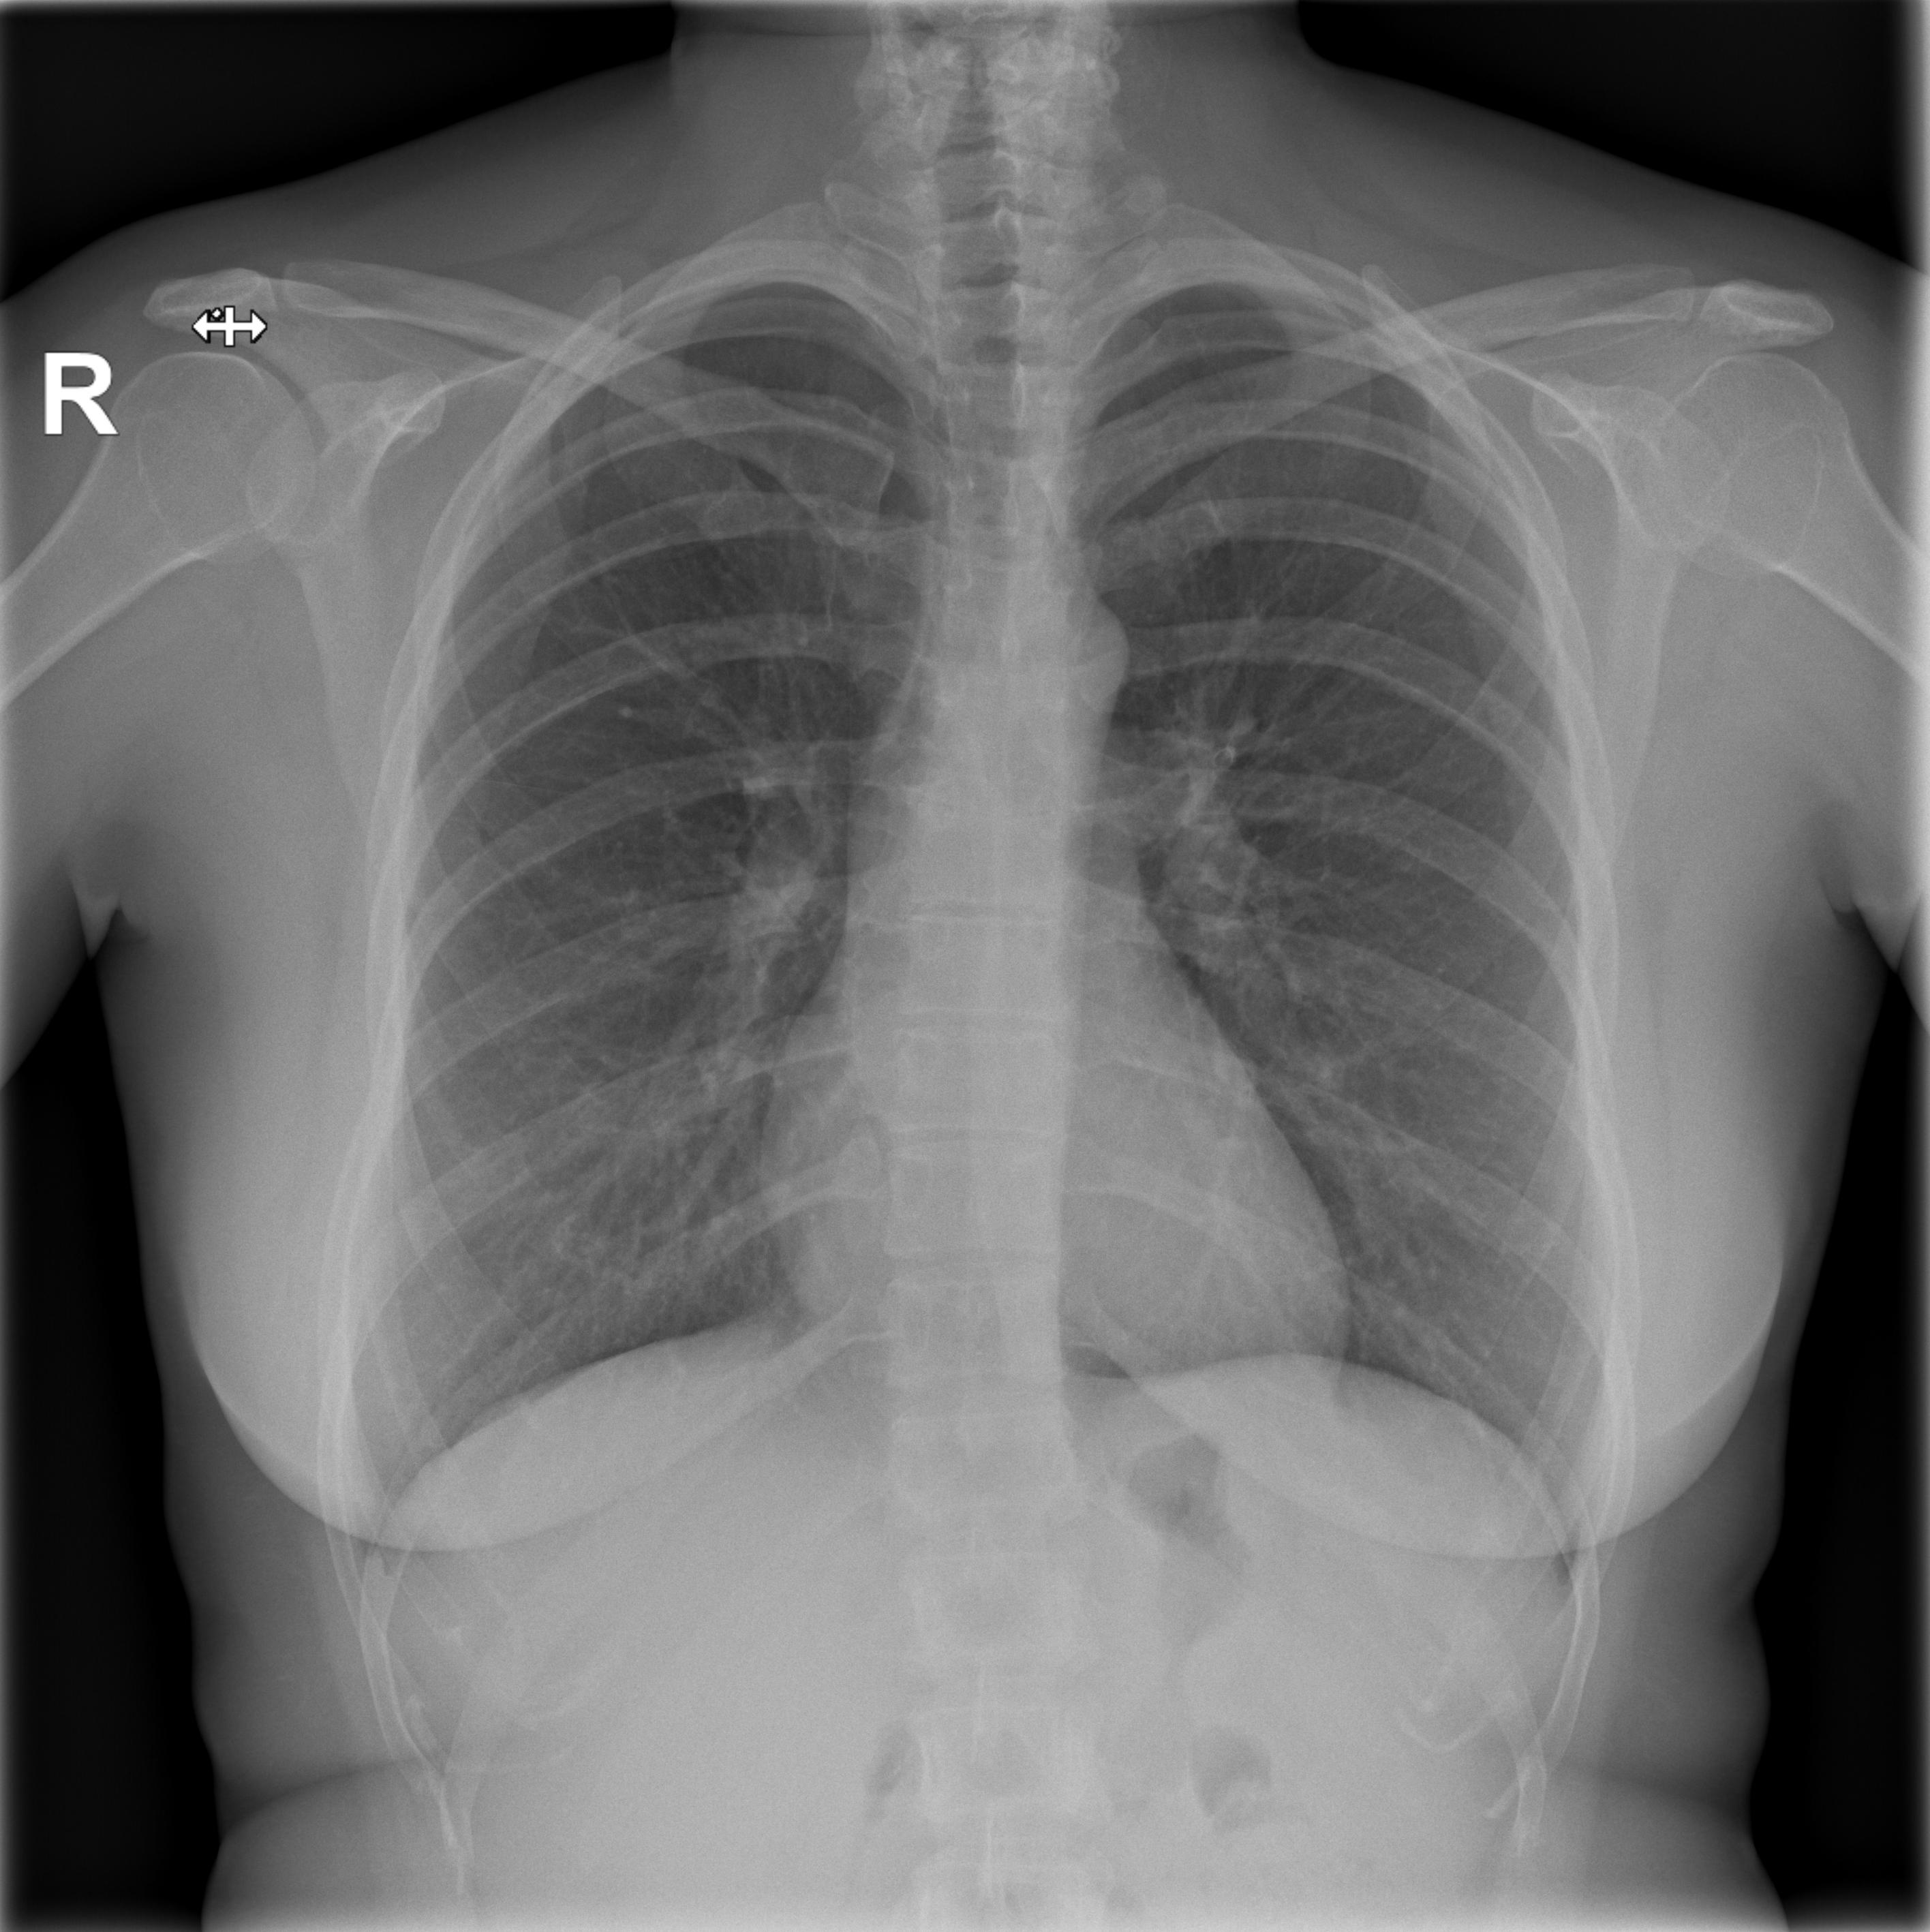

Chemotherapy day (finally) arrived: the sooner I started, the better, obviously. Not sure what happened on the day, but I fainted while getting ready. The pain from the port surgery, the tiredness, the stress of it all, I just went down on my face. My oncologist suspected a pneumothorax (a collection of air outside the lung but within the pleural cavity) so I was sent to radiology for some x-rays.

They checked my lungs during inspiration (first image) and expiration (second image): you can clearly see Portia with the catheter getting into my subclavian vein.

Luckly enough, I didn’t have a pneumothorax, so we went ahead with chemotherapy.